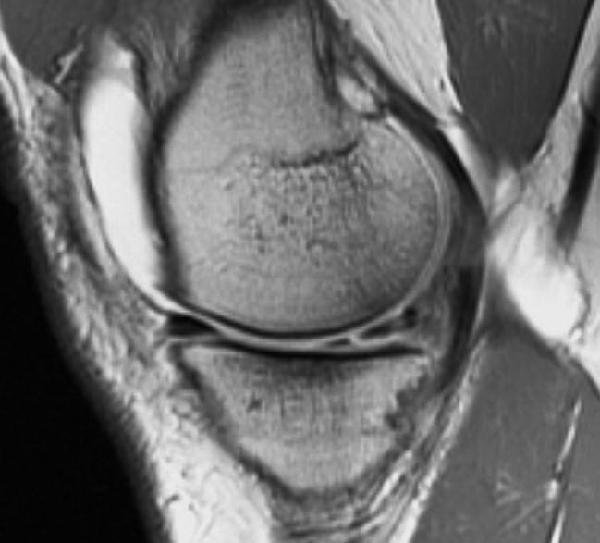

- Investigații imagistice – în special RMN, care evidențiază clar localizarea și tipul rupturii.